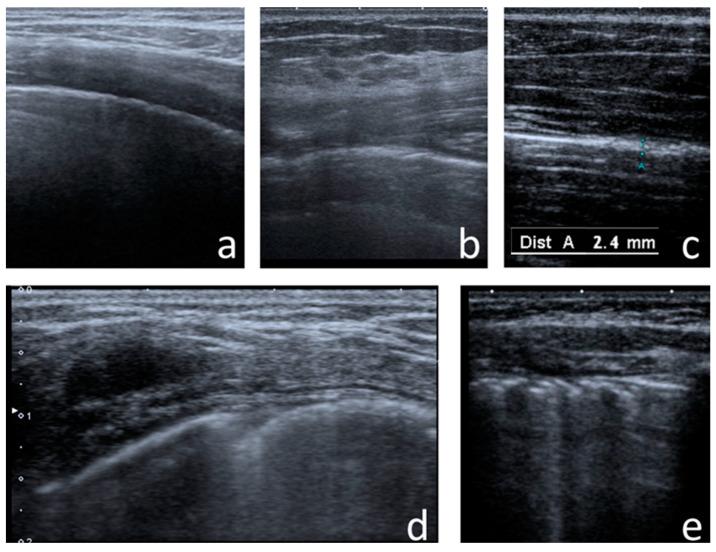

With the increasing longevity of cystic fibrosis (CF), there is a growing need to minimise exposure to ionising radiation in patients who undergo regular imaging tests while monitoring the course of the lung disease. This study aimed to define the role of lung ultrasounds (LUS) in the evaluation of lung disease severity in children with clinically stable CF. LUS was performed on 131 patients aged 5 weeks to 18 years (study group) and in 32 healthy children of an equivalent age range (control group). Additionally, an interobserver study was performed on 38 patients from the study group. In CF patients, the following ultrasound signs were identified: I-lines; Z-lines; single, numerous and confluent B-lines; Am-lines; small and major consolidations; pleural line abnormalities and small amounts of pleural fluid. The obtained results were evaluated against an original ultrasound score. LUS results were correlated with the results of chest X-ray (CXR) [very high], pulmonary function tests (PFTs) [high] and microbiological status [significant]. The interobserver study showed very good agreement between investigators. We conclude that LUS is a useful test in the evaluation of CF lung disease severity compared to routinely used methods. With appropriate standardisation, LUS is highly reproducible.

随着囊性纤维化(CF)患者寿命的延长,在对肺部疾病病程进行监测的同时,尽量减少接受常规影像学检查的患者所受电离辐射的需求日益增加。本研究旨在明确肺部超声(LUS)在评估临床病情稳定的CF患儿肺部疾病严重程度中的作用。对131例年龄在5周至18岁的患者(研究组)以及32例年龄范围相当的健康儿童(对照组)进行了LUS检查。此外,对研究组中的38例患者进行了观察者间研究。在CF患者中,识别出了以下超声征象:I线;Z线;单发、多发及融合的B线;Am线;小实变和大实变;胸膜线异常及少量胸腔积液。将获得的结果与原始超声评分进行对照评估。LUS结果与胸部X线(CXR)结果[高度相关]、肺功能测试(PFTs)结果[相关性高]以及微生物学状态[显著相关]相关。观察者间研究显示研究者之间具有很好的一致性。我们得出结论,与常规使用的方法相比,LUS在评估CF肺部疾病严重程度方面是一种有用的检查方法。通过适当的标准化,LUS具有高度可重复性。